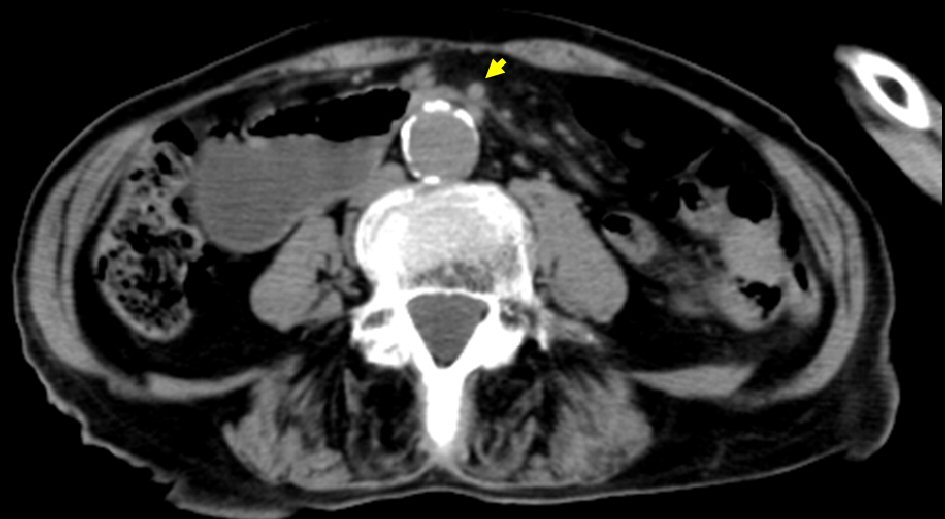

An 89-year-old woman who was admitted to hospital and bedridden due to traumatic acute subdural hematoma was referred to our department with a 3-day history of repeated vomiting since her admission in June 2019. She had no history of significant surgical complications. Examination revealed a body mass index of 17.7 kg/m2 and abdominal distension without tenderness. Abdominal computed tomography (CT) revealed a severely dilated stomach and significant dilatation of the duodenum up to the level of the distal third portion, which was sandwiched between the aorta and SMA (Fig. 1). The angle between the aorta and SMA was 14°, and the aorta-SMA distance was 5 mm, which met the diagnostic imaging criteria for adult SMA syndrome [15]. Upper gastrointestinal endoscopy after nasogastric drainage showed narrowing of the third portion of the duodenum without mucosal abnormality; the endoscope was not able to pass through this site. Fluoroscopy showed a smooth, abrupt obstruction at the third portion of the duodenum. We performed gastrojejunostomy via the MCA technique because her situation did not improve after 1 month of conservative therapy, which included nil per os, nasogastric drainage and enteral nutrition via a W-ED tube (Japan Covidien Corporation, Tokyo), and because the operative risk was high. Written informed consent was obtained from the patient and her family.

![]() Click for large image | Figure 1. Abdominal CT revealed dilatation of the duodenum up to the level of the distal third portion, which was sandwiched between the aorta and SMA (arrow). CT: computed tomography. |